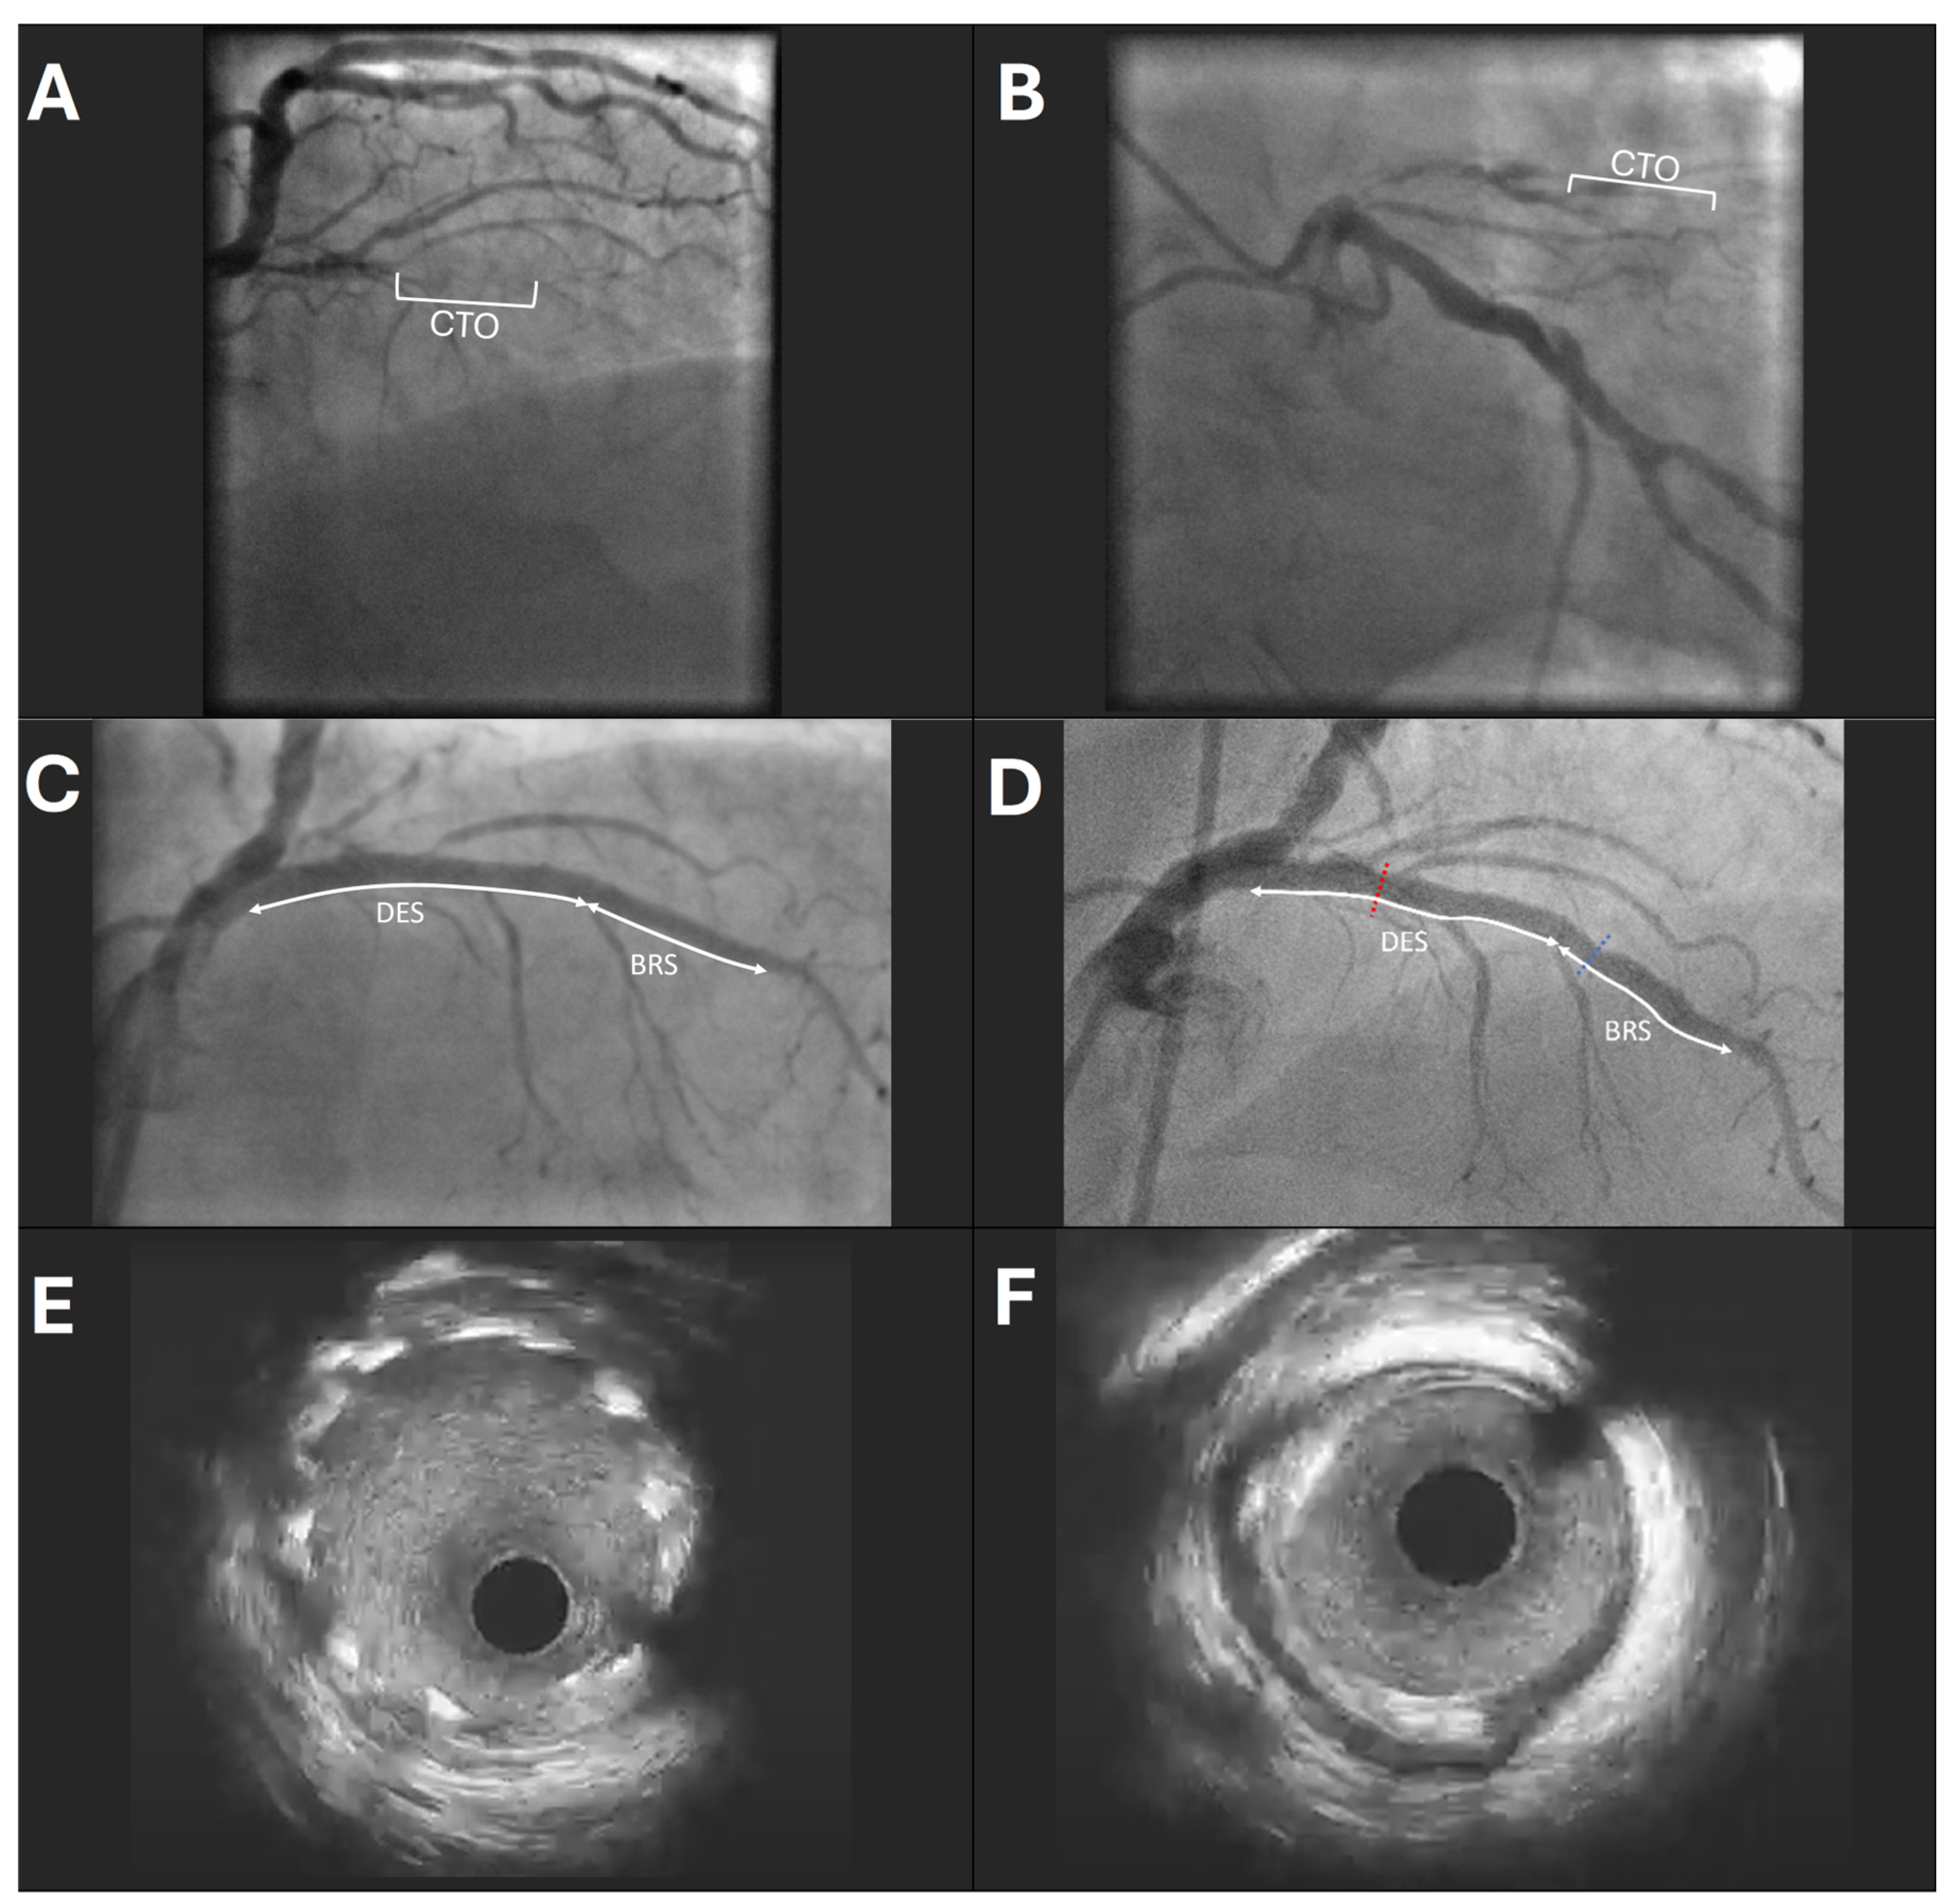

3.2. Procedural Characteristics

| Approach to CTO: | |

| Antegrade | 23 (67.6) |

| Retrograde | 11 (32.4) |

| Type of stents implanted: | |

| 1 DES and 1 BRS | 18 (52.9) |

| 2 DES and 1 BRS | 7 (20.6) |

| 1 BRS only | 7 (20.6) |

| 2 BRS and 1 DES | 2 (5.9) |